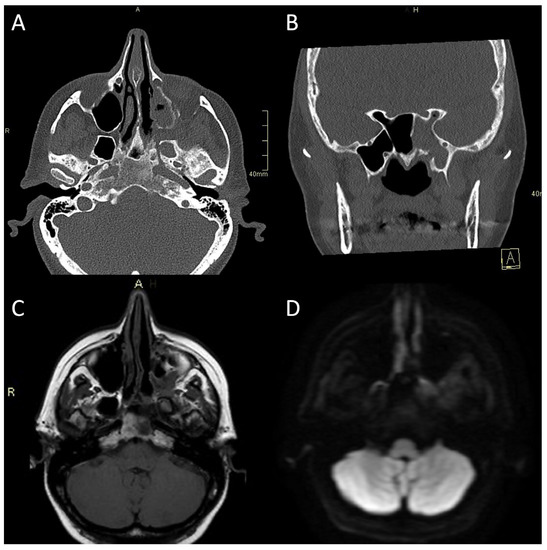

Figure 3.

CT and MRI of a patient with bacterial atypical skull-base osteomyelitis. (A) Axial CT bone algorithm reconstruction showing expanded left pterygopalatine fossa, opacified ipsilateral maxillary, and sphenoid sinus, with mixed erosive and hyperostotic bony changes. (B) Coronal CT bone algorithm reconstruction showing asymmetric expansion and destruction of the left Vidian canal; A—anterior. (C) Axial MRI T1 showing clival bone marrow oedema. (D) Axial MRI DWI showing increased signal in the left pterygoid base, pterygopalatine fossa, and infratemporal fossa. CT: computerised tomography; MRI: magnetic resonance imaging; CE: contrast-enhanced; DWI: diffusion-weighted imaging.